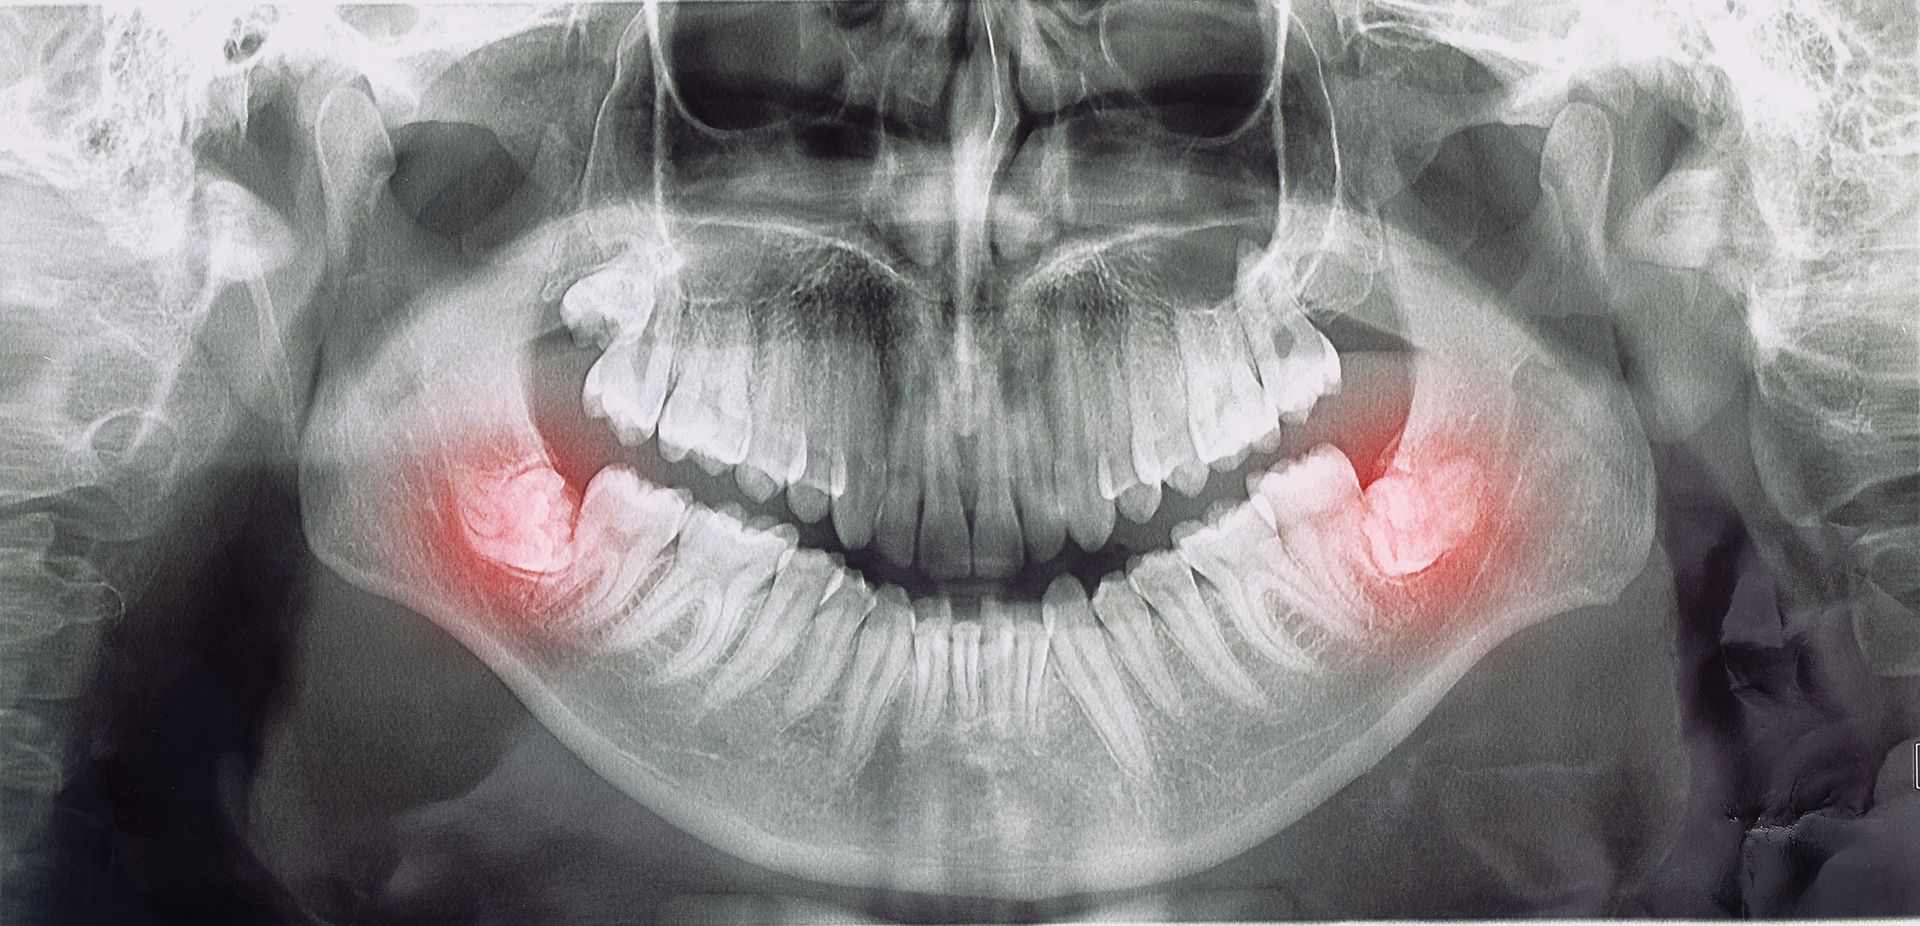

Dans certains cas, les dents ne sortent pas complètement de la gencive. Il est alors recommandé de les enlever de façon préventive avant l’âge de 25 ans. Cette intervention peut prévenir des complications ultérieures (carie de la dent de sagesse et sa voisine, une perte osseuse, une infection, la formation de kystes odontogènes, et autres), car ce sont les risques qui augmentent avec l’âge.